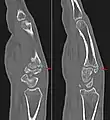

Carpometacarpal bossing (or metacarpal/carpal bossing) is a small, immovable mass of bone on the back of the wrist. The mass occurs in one of the joints between the carpus and metacarpus of the hand, called the carpometacarpal joints, where a small immovable protuberance[1] occurs when this joint becomes swollen or bossed.

The joint between the index metacarpal and the capitate is a fibrous non-mobile joint. Some people have a gene that leads to this growth. It looks like arthritis (bone spurs on each side of the joint) on X-ray. It looks like a ganglion on the hand, but more towards the fingertips.

The carpometacarpal joint is usually found at the base of the second and third metacarpal bones at the point where they meet the small bones of the wrist.[2]

Carpometacarpal boss is uncommon and there is not much scientific data. Its etiology has yet to be fully defined, but can be congenital in the form of an accessory ossicle (os styloideum) or may be acquired from trauma, repetitive use, or degenerative osteophytosis.[3] The condition usually begins to show in the 3rd or 4th decade.